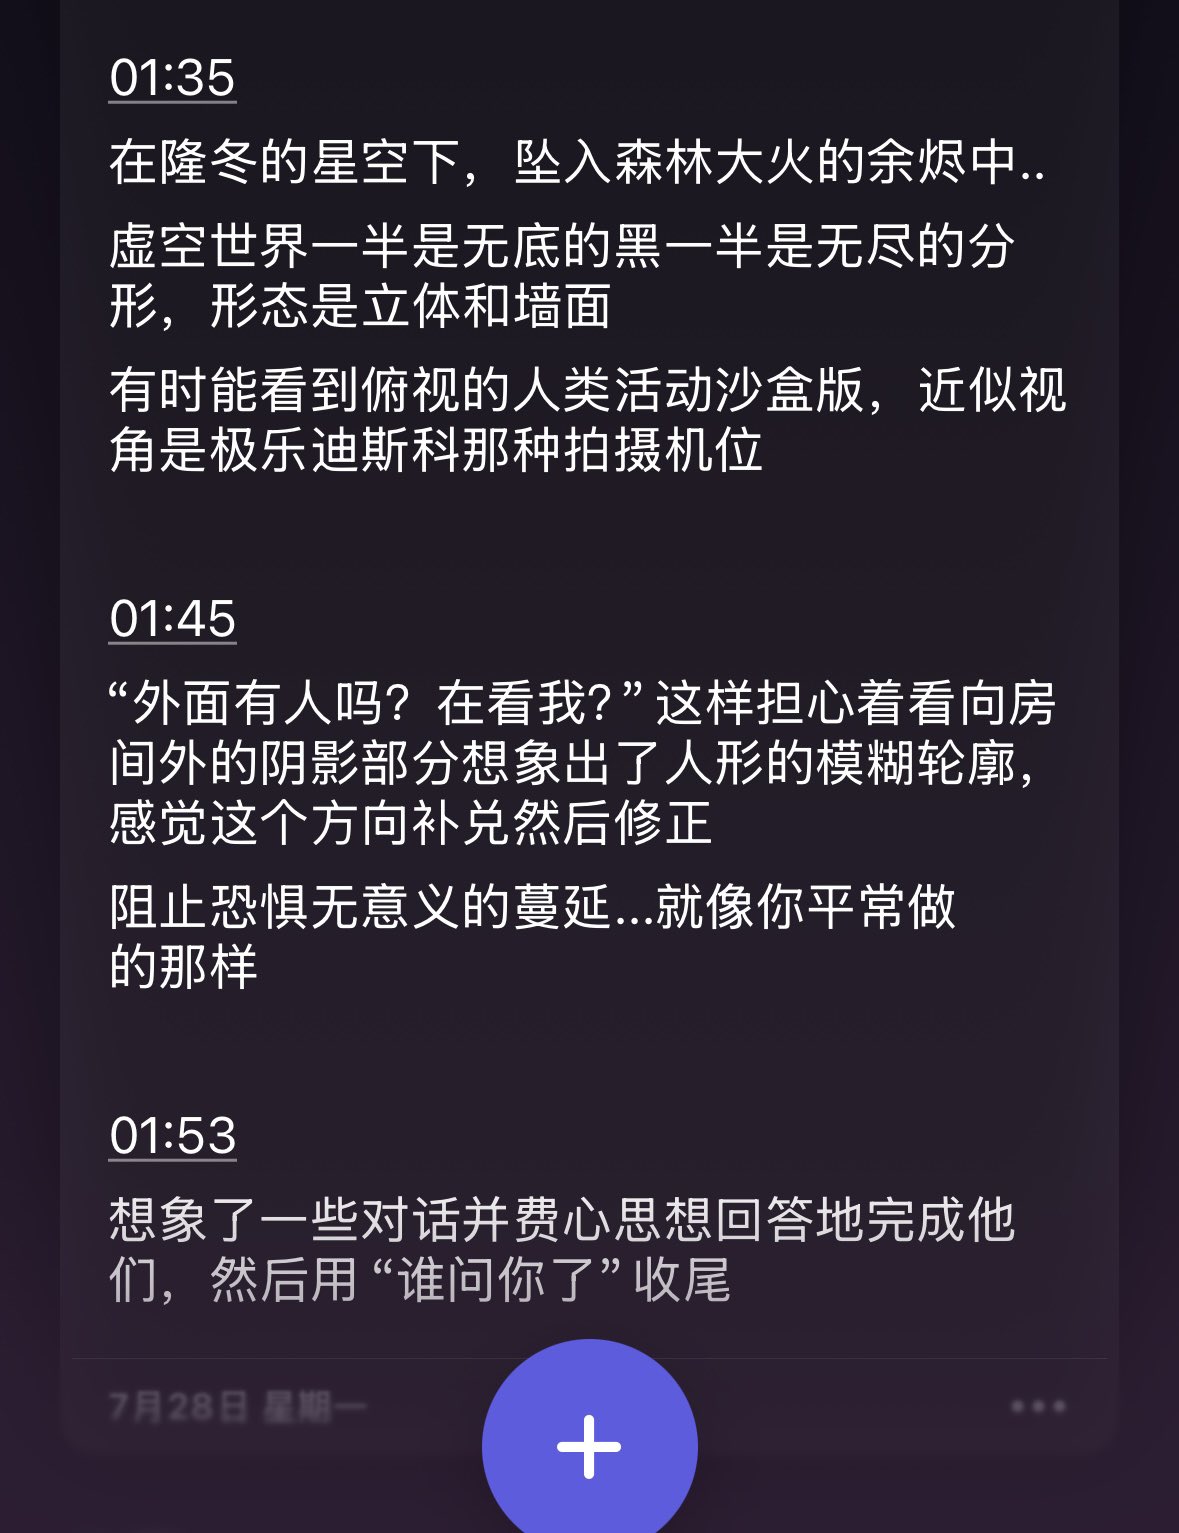

炽烈已极 @AnIncandescence内幻。

2026-01-27 20:34:05 UTC

1,我闭着眼可以看到房间,随着“视线”移动

的一块区域是清晰的,以外是黑白加模糊。

2,我看到一条向上的传送带,上面整齐摆着一个空药盒,不知道尽头在哪里。画面的配文是“讣告”。

3,一个无比巨大的透明药盒。声音很多,像是走马灯的录音带。

炽烈已极 @AnIncandescence04:54

2026-01-28 12:17:50 UTC

4,我知道上面的传送带是哪来的了,这次我闭眼看到我在终末地铺生产线。

05:23

5,旋转,四周是黑色的抖动的线条,我像是躺在夜晚的森林里。

05:34

6,我看到一幅异形拼图,主体是一只彩色羽毛的小鸟,几乎拼好了,但是少了一块。

这次的幻觉连续,不像之前碎碎的,而且我觉得都投射了某些东西

炽烈已极 @AnIncandescence@whitenightX3 journal